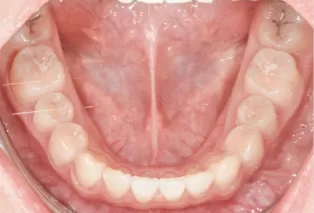

Intraoral photos